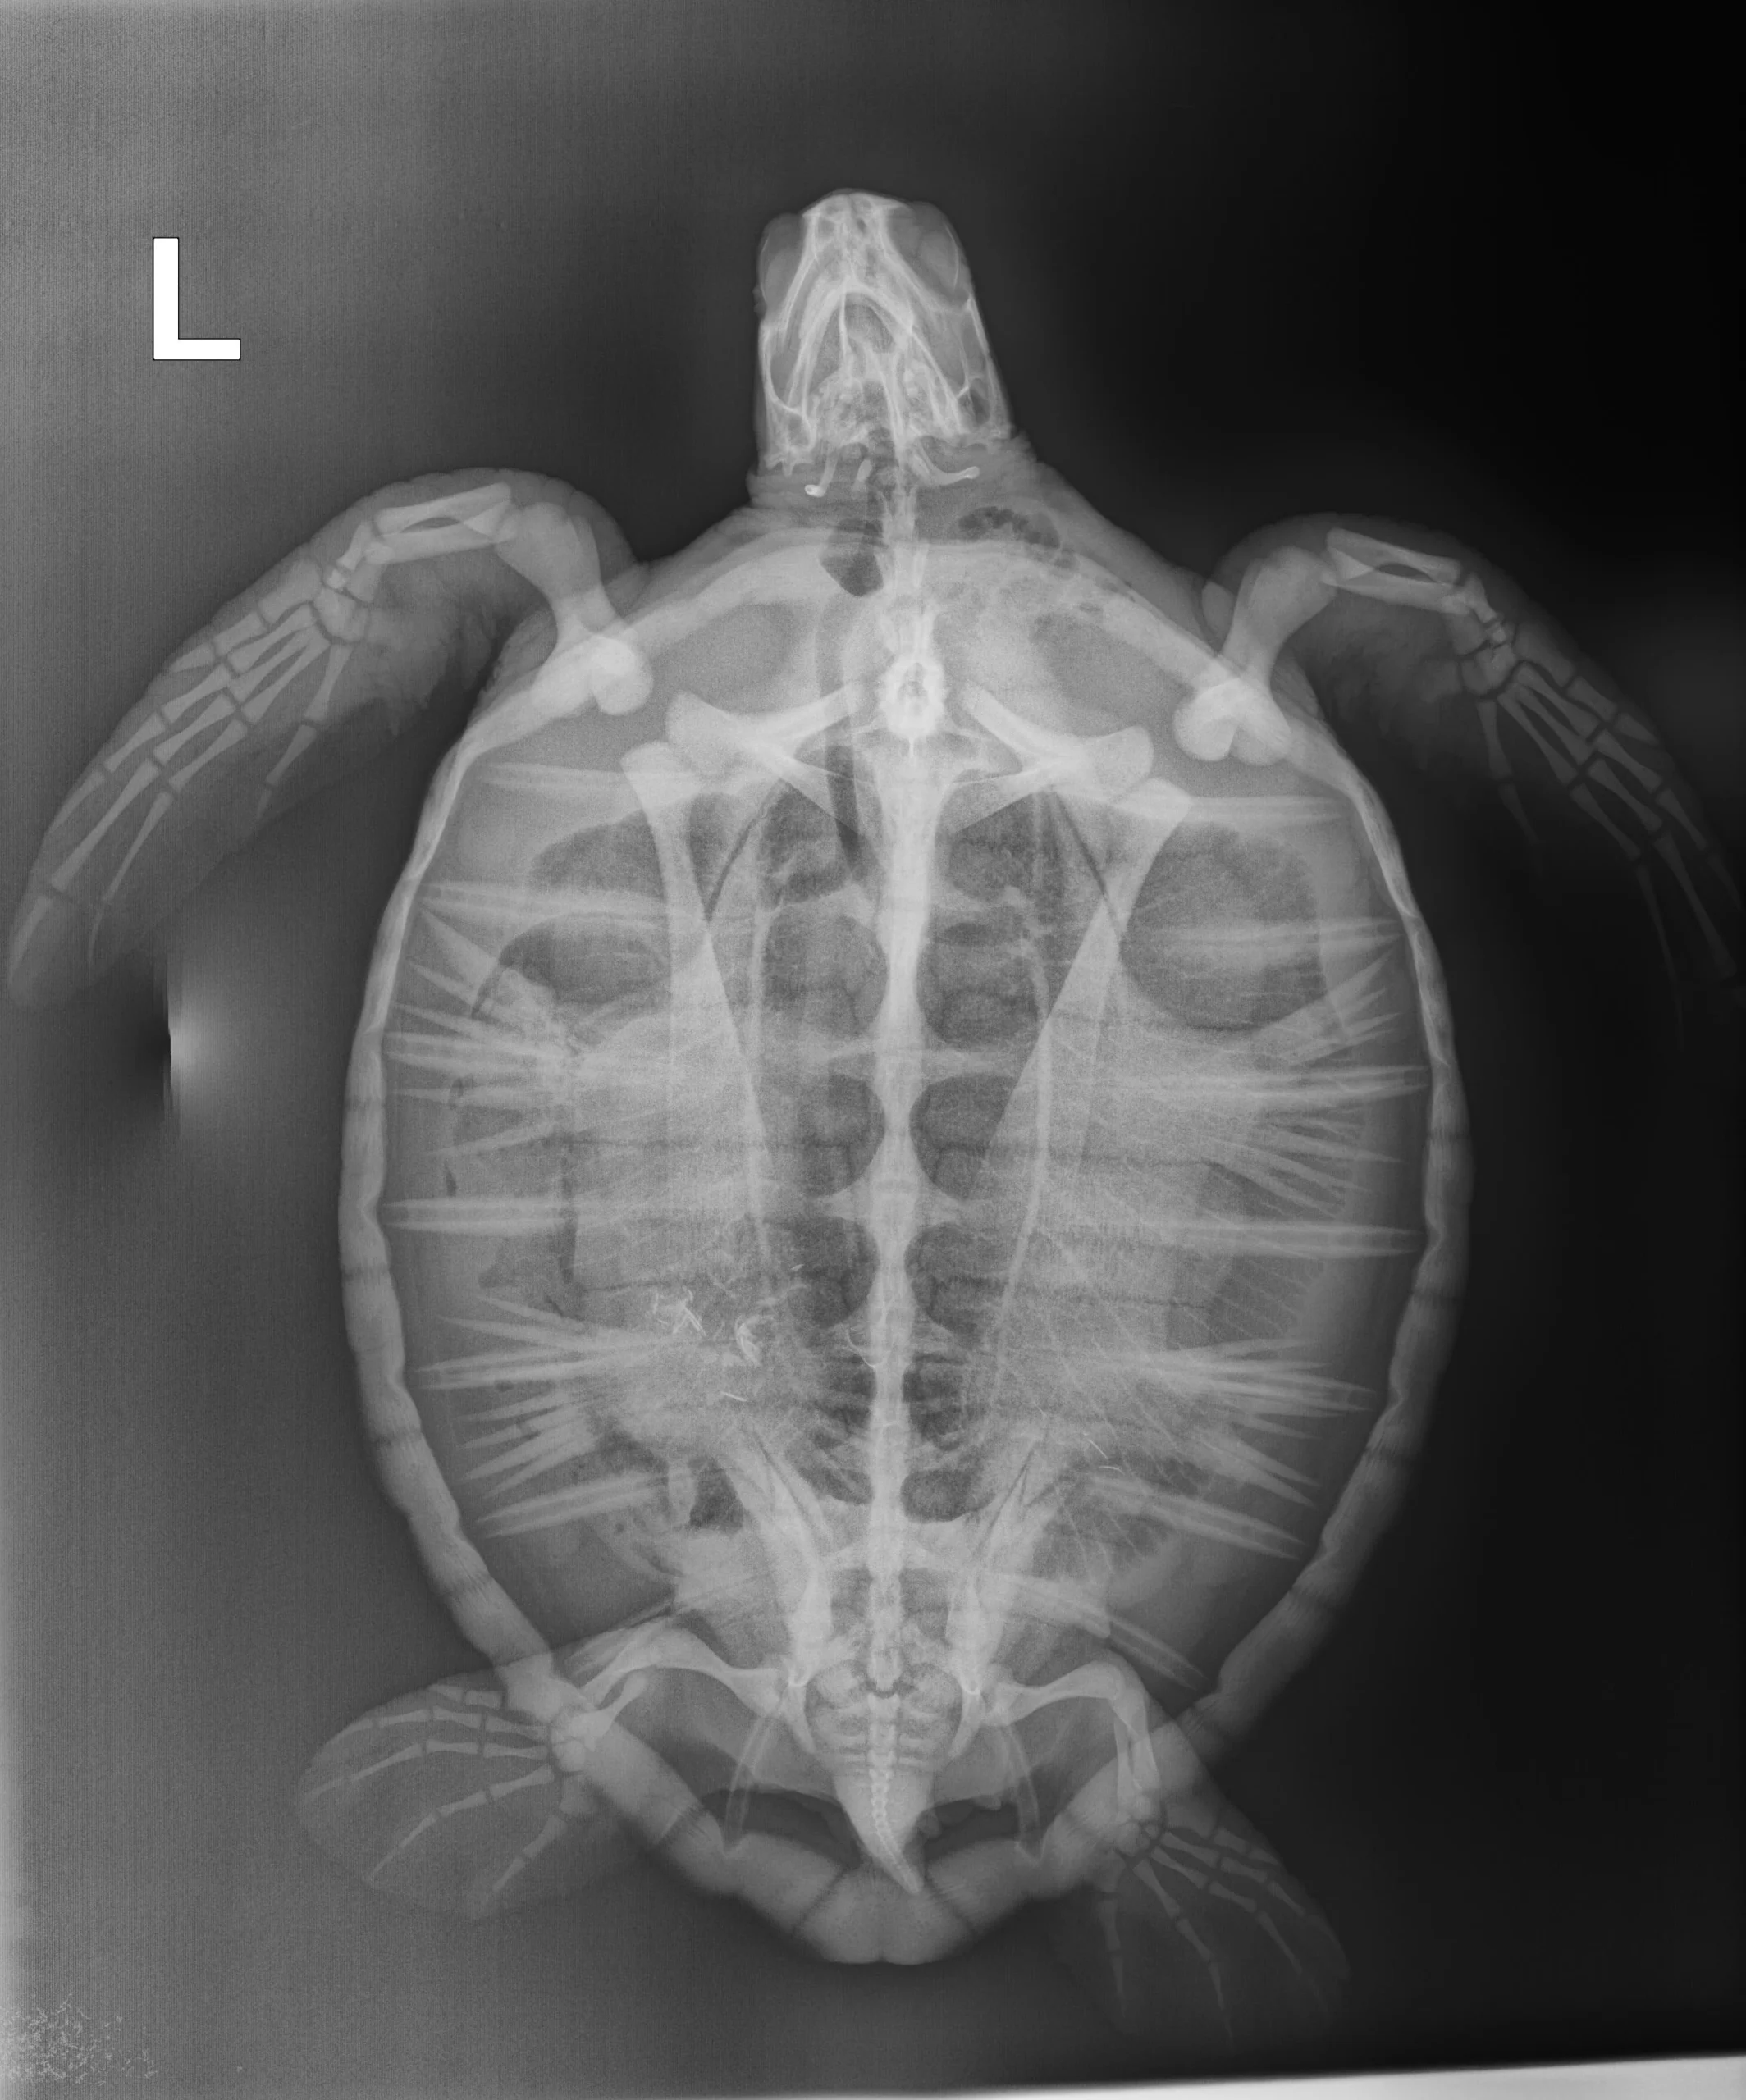

5.9 lbs. non-FP juvenile green

Moderate/severe abrasions on plastron, moderate abrasions on carapace, minor abrasions on all flippers.